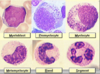

ID cells a, b, e, & f

a. promyelocyte

b. neutrophilic myelocyte

e. neutrophilic band cell

f. segmented neutrophil

I cells b, c, d, e, & g

b. neutrophilic metamyelocyte

c. band neutrophil

d. segmented neutrophil

e. segmented neutrophil

g. neutrophilic metamyelocyte